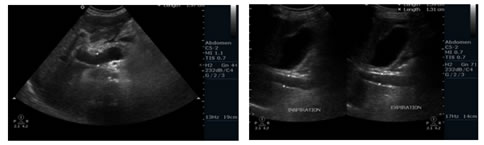

Figure 7: Spectral Doppler USG image: Showing Biphasic flow in Splenic vein; Figure 8: Gray scale and Colour Doppler USG image: Showing Cavernomatous transformation of Portal vein; Figure 9: Gray scale and Colour Doppler USG image; Figure 10: Showing Dilated Coronary vein with Hepatofugal flow; Figure 11: Gray scale and Colour Doppler USG image: Showing GEJ collaterals; Figure 12: Gray scale and Colour Doppler USG image: Showing Lienorenal collaterals; Figure 13: Gray scale and Colour Doppler USG image: Showing Recannalised Paraumbilical vein with hepatofugal flow; Figure 14: Colour Doppler USG image: Showing Absent Colour flow in Portal vein due to Thrombosis

Bolondi, et al9 studied the the caliber of the portal veinin 79 patients with Portal Hypertension and 45 healthy individuals. Portal vein diameter ≥ 1.3 cm was observed in 33/79 cases (41.7%). They concluded that portal vein caliber ≥ 1.3 cm can be considered a fairly characteristic sign of portal hypertension. In a study done by Jeffrey Weinreb, et al10 the mean portal vein diameter in 107 patients was found to be 11 ± 2 mm. They also concluded that portal vein caliber ≥ 1.3 cm can be considered a fairly characteristic sign of portal hypertension.      In a study done by Ditchfield MR, et al11 portal vein diameter ≥ 13 mm was observed in only 41.1% of their study population. In the present study Portal vein diameter > 13 mm was observed in 25/40 cases constituting about 62.5% of our study population. PV diameter ≤ 13 mm was observed in 15/40 cases constituting about 37.5% of our study sample. According to study conducted by Bolondi, et al9 an increase of less than 20% in diameter of portal vein with deep inspiration indicates portal hypertension with sensitivity of 80% and specificity of 100%. In our study respiratory variation of portal vein diameter less than 20% was found in 28/40 cases constituting about 70% of our study sample. 12/40 cases, about 30% of study population showed normal respiratory variation of more than 20% of portal vein calibre. Bolondi, et al found that lack of respiratory variations of portal vein diameter was more sensitive sign of portal hypertension than dilatation of portal vein. In our study Dilated Portal vein > 13mm was found in 62.5% of study population. Respiratory variations of less than 20% of portal vein diameter were noticed in 70% of study population. Hence in our study we found that both Dilated Portal vein > 13mm and Respiratory variations of less than 20% of Portal vein diameter as sensitive signs of Portal Hypertension.